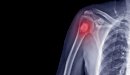

كسور العظام

هي انقطاع في استمراريّة العظام، وعلاجها يكون من خلال إرجاع استمراريّة العظام إلى مكانها الطبيعي، وهناك طريقتان للعلاج:

مضاعفات الكسور

- حدوث إصابات في الأوعية الدموية.

- تقل التروية الواصلة للطرف ممّا يؤدي إلى موت الطرف.

- ضرب العصب ممّا يؤدّي إلى شلل أو فقدان الحس في الطرف نفسه الذي حدثت فيه الإصابة.

- تشوهات في الأطراف؛ ففي بعض الأحيان إذا حدثت إصابة في العمود الفقري يُمكن أن تسبّب عند المريض نوعاً من أنواع الشلل

الثنائي أو الرباعي.